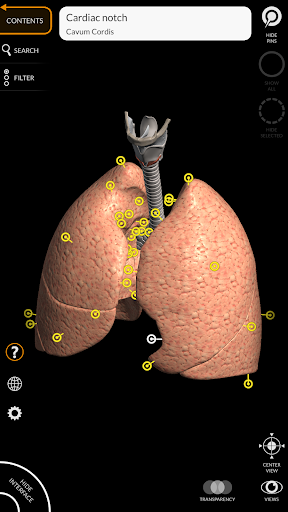

يتيح لك "Anatomy 3D Atlas" دراسة التشريح البشري بطريقة سهلة وتفاعلية.

من خلال واجهة بسيطة وبديهية، من الممكن ملاحظة كل بنية تشريحية من أي زاوية.

تتميز النماذج التشريحية ثلاثية الأبعاد بتفاصيل خاصة ودقة تصل إلى 4K.

نماذج تشريحية ثلاثية الأبعاد

• الجهاز التنفسي

• تدوير وتكبير كل نموذج في مساحة ثلاثية الأبعاد

• خيار إخفاء أو عزل نموذج واحد أو نماذج متعددة مختارة

• وظيفة الشفافية

• من خلال تحديد نموذج أو دبوس، يظهر المصطلح التشريحي ذي الصلة